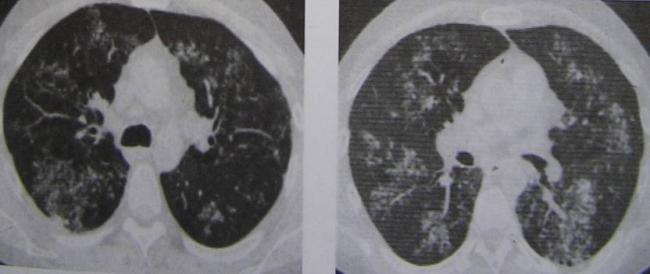

Очаговые изменения

Очаговые изменения в лёгких могут быть разного размера. Очаги мелкого диаметра 1-10 мм выявляются при различных диффузных патологиях лёгочной ткани. Очаги с высокой плотностью и довольно чётки краями в основном наблюдаются в интерстиции лёгкого. Различные очаги низкой плотности, напоминающие матовое стекло, с нечёткими контурами возникают при патологических изменениях в респираторных отделах дыхательных органов.

Нужно учитывать, что плотность и размер очагов имеет слабое диагностическое значение. Для постановки диагноза более важным может быть распределение патологических процессов в лёгочной ткани:

- Перилимфатический очаг – часто наблюдается в бронхах, сосудах, в междольковых перегородках и листках плевры. В таком случае видны неровные контуры анатомических структур, при этом перегородочки и стенки бронхов несколько утолщены, как и стенки сосудов. Подобные патологические изменения часто встречаются при туберкулёзе, силикозе, саркоидозе и карциноматозе. При этих патологиях очаги небольшие и не превышают 2-5 мм. Состоят такие очаги из гранулем или метастатических узелочков, они наблюдаются вдоль лимфатических узелков в ткани лёгких и плевре.

- Полиморфный очаг. Такие очаговые образования в ткани лёгких возникают при туберкулёзе. В этом случае КТ позволяет увидеть участки разной плотности и размеров. В некоторых случаях такая картина наблюдается при онкологических патологиях.

- Центрилобулярные очаги. Наблюдаются в артериях и бронхах или в непосредственной близости от них. Они могут быть довольно плотными, хорошо очерченными и однородными. Изменения лёгочной ткани такого типа наблюдаются при пневмониях, эндобронхиальном туберкулёзе и разных видах бронхита, преимущественно бактериального происхождения. Есть и другой тип центрилобулярных очагов, в этом случае лёгочная ткань имеет мелкие уплотнения и похожа на матовое стекло.

- Периваскулярные очаги – это патологические образования, которые находятся в непосредственной близости от кровеносных сосудов. Такое состояние наблюдается при онкологических патологиях и туберкулёзе. Очаги могут быть как единичные, так и множественные.

- Хаотично расположенные очаги. Такие образования характерны для патологических гематогенных процессов. Это может быть гематогенная инфекция, туберкулёз или метастазы гематогенного типа. Большие множественные очаги, размером около 10 мм, частенько наблюдаются при септических эмболиях, гранулематозе, грибковых инфекциях и метастазах. Все эти заболевания имеют некоторые отличия, по которым их можно дифференцировать.

- Субплевральные очаги – это патологически изменённые участки, расположенные под плеврой. Наблюдение таких участков на снимке всегда говорит о развитии туберкулёза или онкологических заболеваний.

При очаговых заболеваниях участки патологически изменённой ткани могут быть разными по размерам. Они могут быть мелкими, размером не более 2 мм, средними – диаметром до 5 мм и крупными, размер последних превышает 10 мм.

Патологические очаги бывают плотными, средней плотности, а также рыхлыми. Если в лёгких наблюдаются единичные уплотнения, то это может быть как возрастным изменением, которое не представляет опасности для человека, так и опасным заболеванием. Если наблюдаются множественные очаги, то здесь речь идёт о воспалении лёгких, туберкулёзе или редких формах онкологических заболеваний.